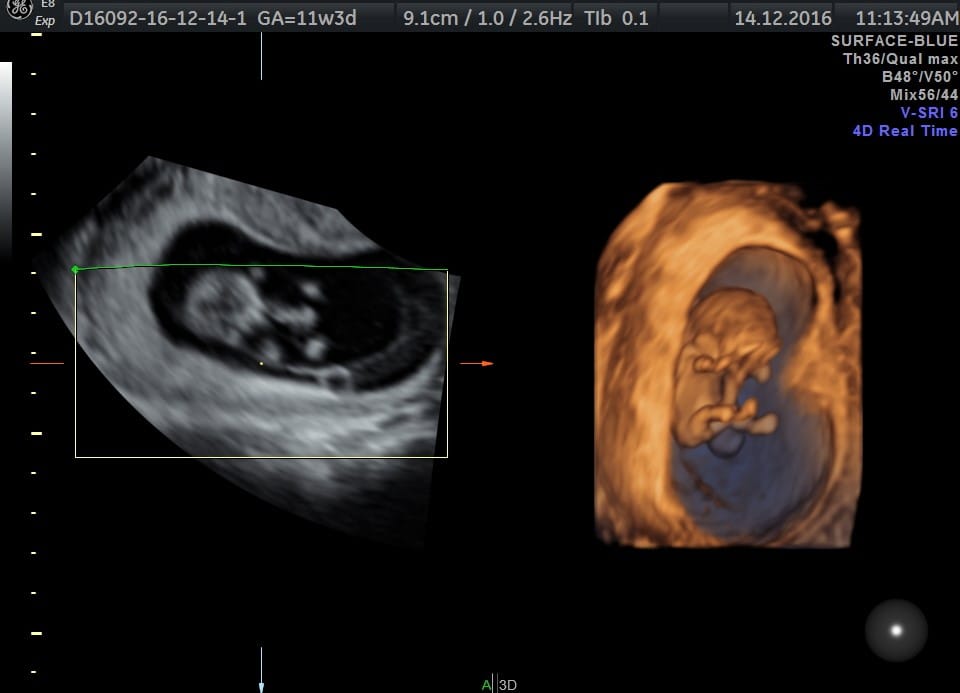

Nosečniški dnevnik 2: Pregled nuhalne svetline

14. decembra je prišel dan, na katerega sem bila naročena za pregled nuhalne svetline. Tokrat sem izbrala zdravstveni center Dravlje. Pri hčerki sem bila pri dr. Strahovi v Domžalah in sem bila zadovoljna, zakaj tokrat Dravlje? Ker mi je bilo na 3D pregledu pri hčeri tam res super.

| Trajanje nosečnosti | 11 tednov 4 dni | 11 tednov 3 dni |

| Starost mamice | 21 | 23 |

| Srčni utrip | 173 | 170 |

| Dolžina od glavice do trtice | 5,6 cm | 4,5 cm |

| Nuhalna svetlina | 1,7 mm | 1,2 mm |

| Premer glave | 16,2 mm | 14,8 mm |

| Tveganje za trisomijo 21 | 1:19494 | 1:4793 |

| Tveganje za trisomijo 18 | 1:14650 | 1:6425 |

| Tveganje za trisomijo 13 | 1:22140 | Večje od 1:20000 |